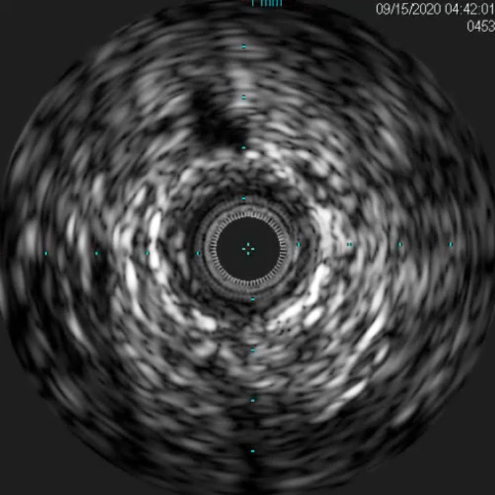

腔内超声证实:铁支架完全张开、贴壁良好,无明显残余狭窄。